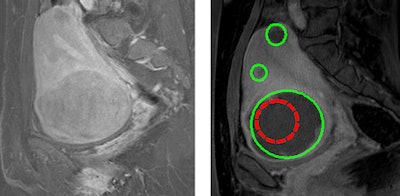

| T1-weighted contrast-enhanced MR images before (left) and after (right) treatment. The red region encloses the targeted treated area; the green regions show the nonperfused volume. Images courtesy of University Medical Center Utrecht. |

The first patient had four small fibroids and two large fibroids, one of which was already devascularized. Treatment focused on the remaining vascularized large fibroid. Following targeted vessel ablation, the large fibroid exhibited 84% devascularization. The researchers also noted complete devascularization of four small fibroids remote from the heated region.

While the total treated volume was 50 mL, the resulting nonperfused volume (determined immediately after treatment) was 211 mL, 4.2 times higher than expected based solely on the thermal dose distribution. The researchers propose that this could be due to the heat causing vessel constriction, which results in decreased cooling by blood, with the increased temperature inducing thermal coagulation of the vessel wall. This, in turn, induces downstream necrosis of fibroid tissue.

The second patient had two large fibroids. In this case, targeted vessel ablation resulted in 90% and 70% devascularization of the treated fibroids. Here, the truly ablated volume was 122 mL and the resulting nonperfused volume was 282 mL, 2.3 times higher than expected based on the thermal dose distribution.